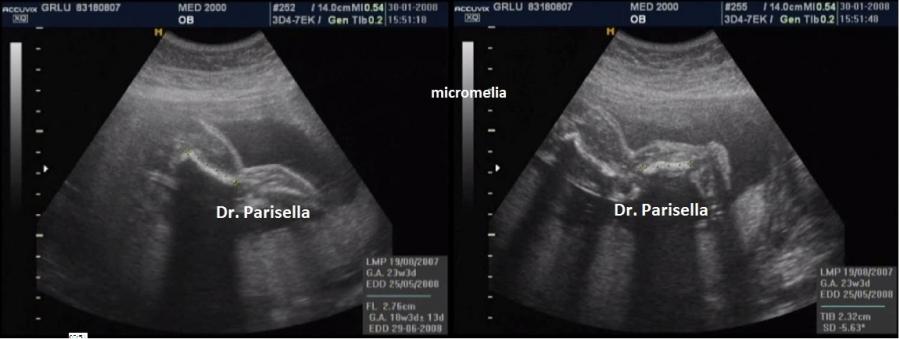

E' caratterizzata da un accorciamento prevalente del femore (rizomelia), anche se sono interessate tutte le ossa lunghe (micromelia) e le ossa delle mani e dei piedi (brachidattilia); la testa è grossa (macrocefalia/macrocrania) con bozze frontali prominenti e ponte nasale depresso. La diagnosi ecografica precoce non è possibile. Spesso infatti l'acondroplasia può essere sospettata o confermata solo in fase avanzata di gravidanza in quanto la micromelia si manifesta tardivamente con un accrescimento delle ossa lunghe inferiore al 5° percentile evidente solo nel III trimestre. La diagnosi può essere facilitata in caso di storia familiare positiva per tale patologia. Alcuni studi hanno riportato l'associazione con la NT aumentata.

1. micromelia: è il segno più evidente, con gli arti inferiori al 5°percentile dopo la 20a-22a settimana; vi è anche brevità rizomelica che interessa principalmente i femori.